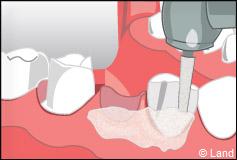

Pour réaliser un bridge, une première étape consiste à préparer les piliers afin de les réduire et les rendre parallèles. Si elles sont trop abîmées, le chirurgien-dentiste peut avoir à reconstruire les dents de soutien.

Vient ensuite la réalisation de l’empreinte dentaire. Cette empreinte permet de réaliser un modèle de vos dents, à partir duquel le bridge est confectionné par le laboratoire de prothèse.